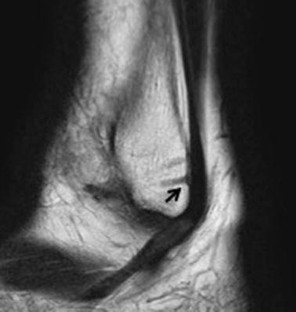

One hundred eleven ankles of 98 patients who had undergone three-dimensional CT scans for foot or ankle disorders without deformity of the fibula were assessed (59 males, 52 females; median age 25.5 years; age range 12–78 years). The shortest distance from the insertion point of the suture anchor to the deepest point of the fossa/top of the convex aspect of the fibula was measured on the axial plane, tilting from the longitudinal axis of the fibula at 90°, 75°, 60°, and 45°. The distance from the insertion point of the suture anchor to the posterior surface of the fibula was also measured in a direction parallel to the sagittal plane of the lateral surface of the talus on the axial plane, tilting from the longitudinal axis of the fibula at 90°, 75°, 60°, and 45°.

The posterior fossa was observed in all cases on the 90° and 75° images. The distance from the insertion point to the posterior surface of the fibula in the parallel direction was 15.0 ± 3.4 mm at 90°, 17.5 ± 3.2 mm at 75°, 21.7 ± 3.3 mm at 60°, and 25.7 ± 3.6 mm at 45°. The posterior points in the parallel direction were located on the posterior fossa in 36.0% of cases at 90°, in 12.6% at 75°, and in 0.0% at 60° and 45°.

The suture anchor should be directed from anterior to posterior at an angle of <45° to the longitudinal axis of the fibula, parallel to the lateral surface of the talus, to avoid passing through the fibula.